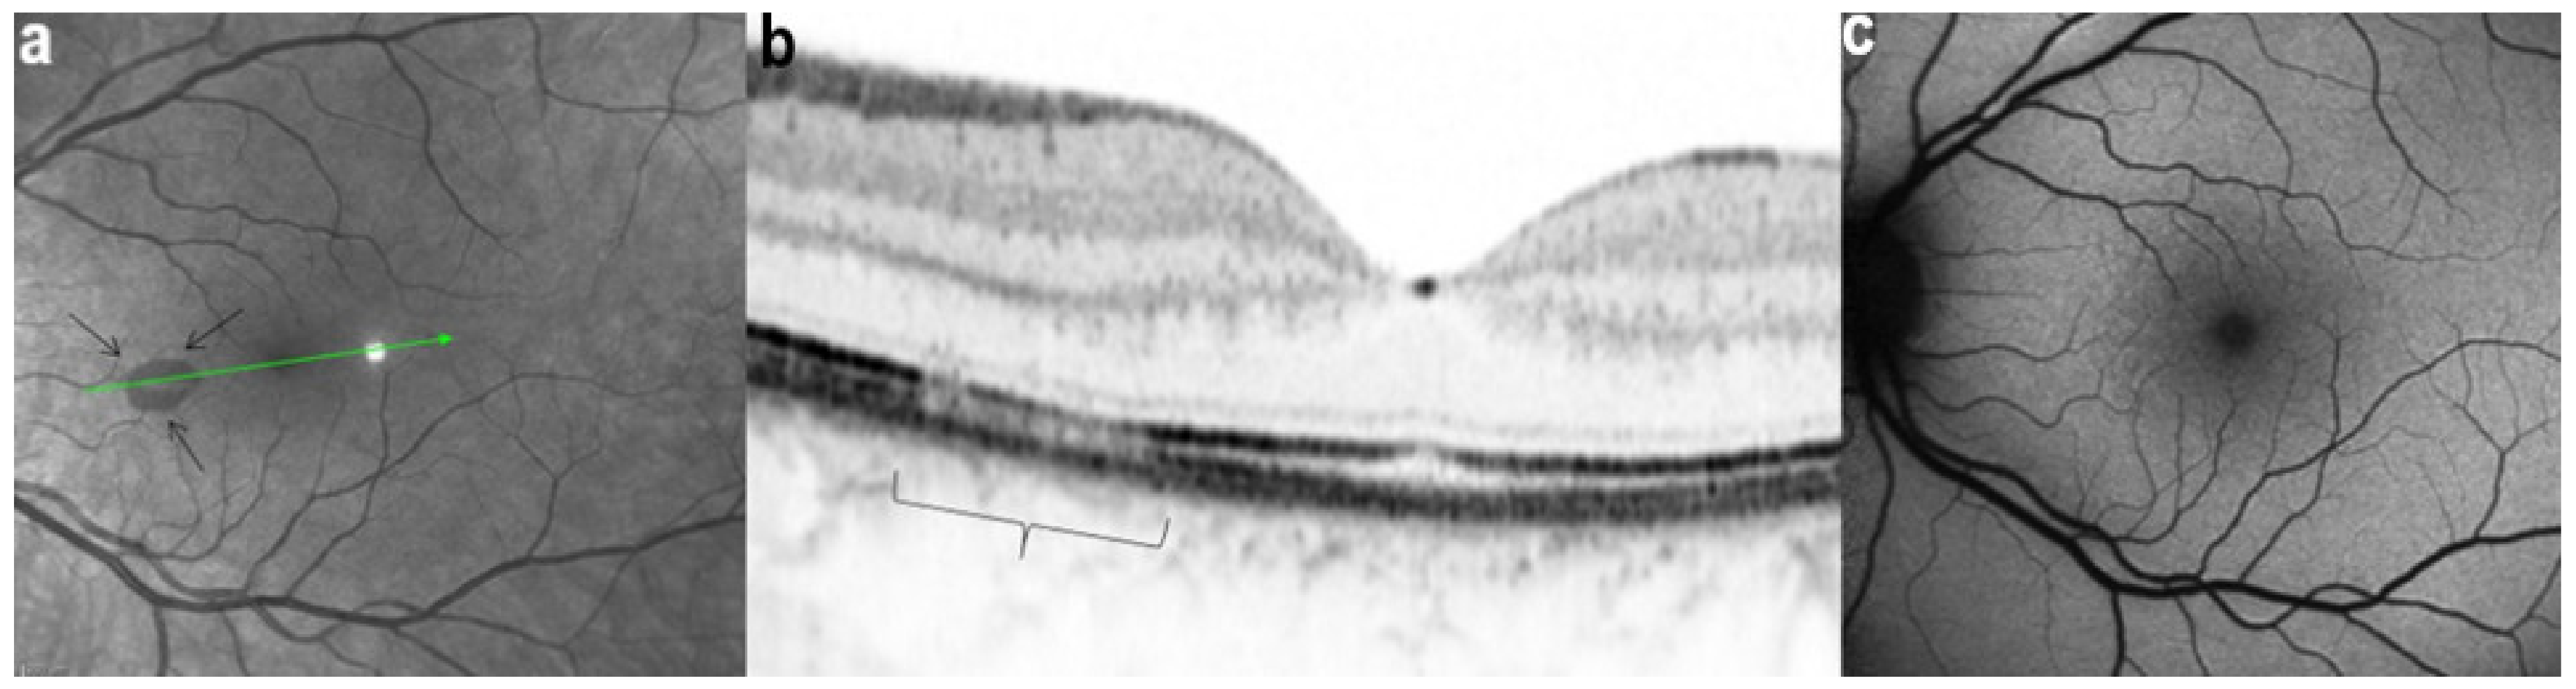

Acute macular neuroretinopathy (AMN) is a rare, outer retinal disease of unknown origin affecting typically young women who complain of paracentral scotomas mono or bilaterally and often occurring with oral contraceptive use. Visual loss is variable. As described by Bos and Deutman [77], the fundus examination reveals distinctive lesions characterized by macular reddish-brown, wedge-shaped lesions corresponding to scotomas referred by the patients (Figure 29).

However, these typical lesions are not always clearly visible on fundoscopy while they are seen more precisely when using the near infrared reflectance (NIR-R) imaging mode that demonstrates sharply demarcated, hyporeflective lesions more definite than those found on fundoscopy [78]. Blue-light fundus autofluorescence (488 nm, lipofuscin related) (BAF), fluorescein angiography (FA) and indocyanine green angiography (ICGA) are usually not significant, while near infrared autofluorescence (787 nm, melanin related) (NIR-FAF) can show abnormalities [78]. Together with the NIR-R, the spectral-domain optical coherence tomography (SD-OCT) represents a very useful new imaging technology to diagnose AMN demonstrating that the outer retina is primarily affected. In the early phase of the disease, OCT shows a transient, localized hyperreflectivity at the outer plexiform layer (OPL)/outer nuclear layer (ONL) [79] (Figure 30). In a short time, the hyperreflectivity is replaced by focal abnormalities of the ellipsoid zone (EZ) and interdigitation zone (IZ) that are often associated with thinning of the ONL (Figure 31 and Figure 32) In addition, electrophysiologic analysis also with multifocal electroretinography has clearly localized the lesion impact at the level of the outer retina [80]. AMN has good prognosis with a slow, progressive improvement of the symptomatology. Macular lesions can persist for a long time.

AMN is often put in the group of choriocapillaritis diseases, which is not the case. It is a rare macular disease of the outer retina. It can be unilateral or bilateral with an accompanying paracentral or central scotoma with or without visual loss. BAF, FA, and ICGA are mostly normal. Retinal capillary ischaemia has been proposed as a possible mechanism. SD-OCT findings suggest that the outer retina is the location of the pathology including hyper-reflectivity of the OPL and ONL, disruption of ellipsoid zone (EZ), and interdigitation zone (IZ) and subsequent thinning of the ONL. The introduction of OCTA has more clearly demonstrated retinal aetiology. As the patients are mostly young women, the main differential diagnosis for AMN is retrobulbar optic neuritis.